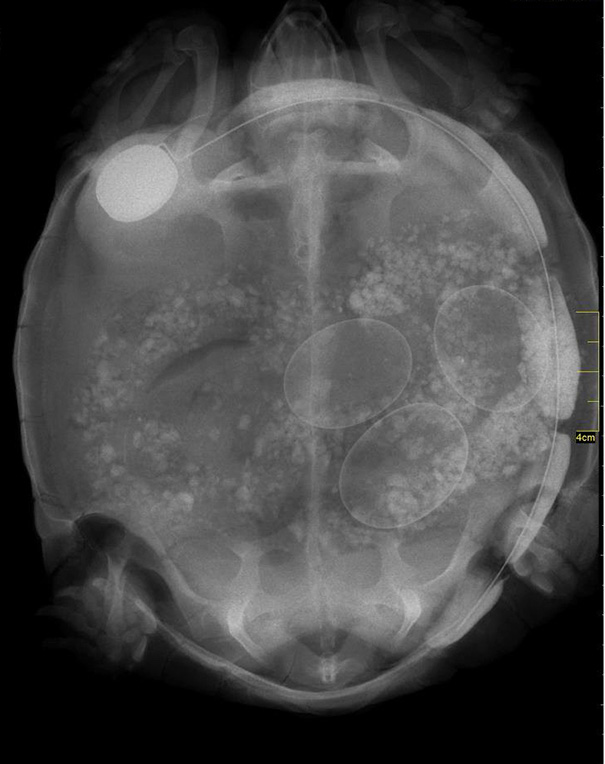

We Just Found Out That One Of Our Transmitted Tortoises Is Pregnant